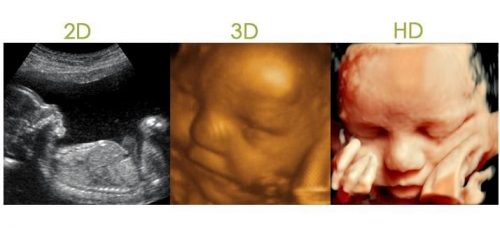

Una ecografia es una prueba con método ultrasonido, esto es, una técnica de imágenes no invasivas que permite ver dentro del cuerpo humano con cierta precisión. Las ecografias en 3 D una imagen con volumen y fijo. Las ecografias en 4D son más precisas, son como las 3D pero con movimiento, se denominan ecografias en tridimensionales en tiempo real. Se pueden hacer en cualquier momento del embarazo.

Las ecografias en 5D las imágenes son más nítidas y con una mayor resolución. Se utilizan sondas de ancho mayor que permiten ver en película en realidad virtual y HD a tu bebé con una precisión mucho más fina. Empresas de 4D se están adaptando a hacer ecografías 5D en pantalla gigante y como una película. (Película en 5D de un BEBÉ de 15 semanas de embarazo)